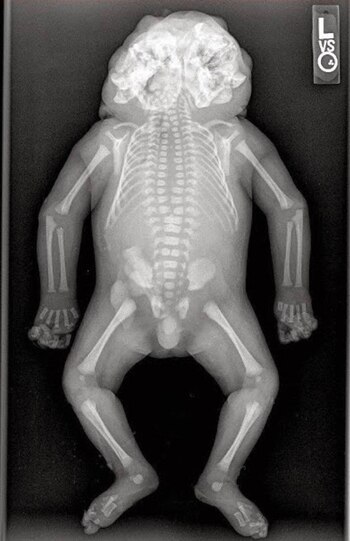

Más allá de la leyenda que existe entorno a Edward Mordrake, lo cierto es que esta malformación genética existe y tiene el nombre de Diprosopia. Esta anomalía genética (muy extraña, por cierto) implica la duplicación de varios rasgos de la cabeza, incluyendo toda la cara.

Por lo general son partes concretas, como los ojos, nariz o boca. Los bebés que nacen con esta anomalía no logran vivir más allá de segundos o minutos luego de su nacimiento, netamente por temas anatómicos.

La diprosopia es provocada por el fallo de un gen que está encargado de dar una forma correcta a la estructura del cráneo. Cuando este falla, el desarrollo se vuelve completamente anómalo.

La principal diferencia con los gemelos parásitos es que en la diprosopia, los rostros provienen del mismo cuerpo. No se trata de siameses que no han podido separarse, sino que son la misma persona.